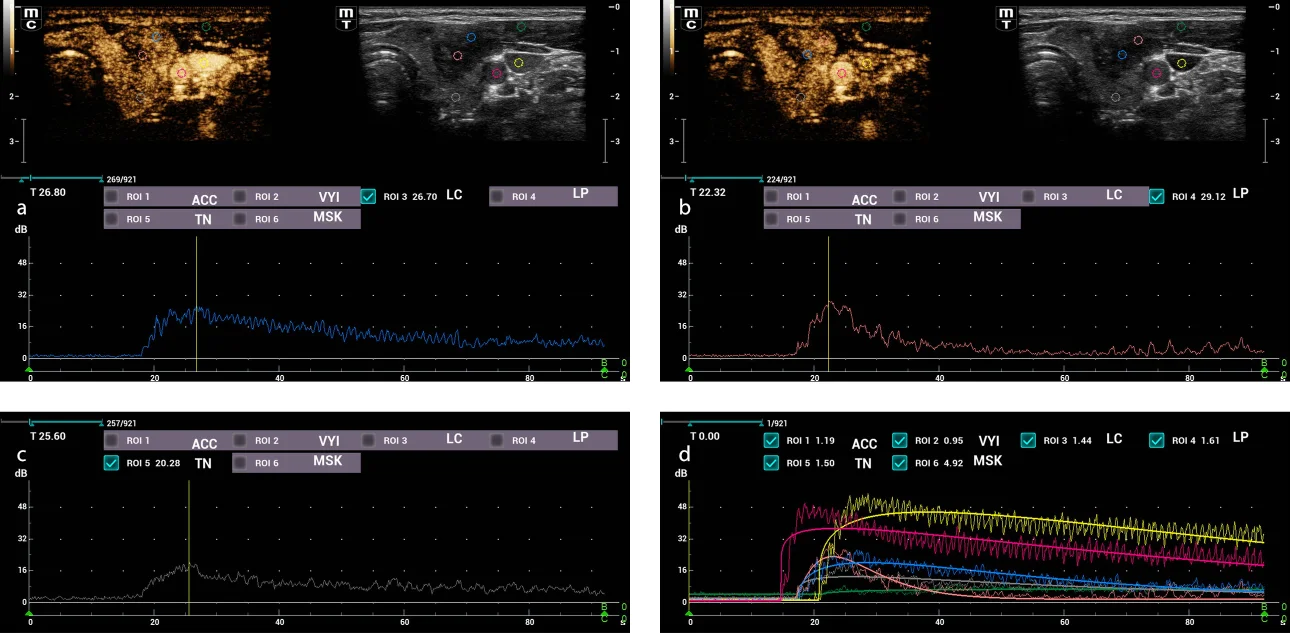

Fig.4. Enhacement curves analysis . In the upper images different ROIs were placed in the central and peripheral region of the thyroid nodule, as well as in the common carotid artery, internal jugular vein, thyroid parenchyma and adjacent musculature.

Fig.4. Enhancement curves analysis. In the upper images different ROIs were placed in the central and peripheral region of the thyroid nodule, as well as in the common carotid artery, internal jugular vein, thyroid parenchyma and adjacent musculature. (a) Central zone of the thyroid nodule with peak time of 26.8 s and maximum intensity of 26.7 dB. (b) Peripheral zone of the thyroid nodule with peak time of 22.3 s and maximum intensity of 29.1 dB. (c) Adjacent thyroid parenchyma with peak time of 25.6 s and maximum intensity of 20.3 dB. (d) Graphs of all the ROIs analyzed, where a maximum intensity and early washing of the peripheral region of the thyroid nodule with respect to the adjacent thyroid parenchyma is observed.

During the diagnostic process, thyroid ultrasound was performed using the Mindray Resona I9 system. A solid, hypoechoic nodule was observed on the left side which was wider than high and had apparent extrathyroid extension and punctate echogenic foci. Additionally, internal vascularity was observed upon application of color Doppler. This nodule was evaluated as ACR TI-RADS 5 based on the findings (Fig. 1). Similarly, the Smart Thyroid AI of Resona i9 ultrasound system program was used to measure and analysy malignant signs and yielded comparable findings, except for the extrathyroidal extension which was assessed as having lobed/irregular borders. However, it also garnered an ACR TI-RADS 5 score (Fig. 2). The elastography examination indicated a heterogeneous appearance with an Emax stiffness of 40.53 kPa . Finally, the CEUS revealed that the lesion was heterogeneously iso-enhanced in comparison with thyroid parenchyma that showed early washout at 45 seconds (Fig. 3). The central portion of the nodule achieved peak intensity of 26.7 dB at 26.8 seconds, correspondingly; while the peripheral portion achieved peak intensity of 29.1 dB at 22.3 seconds (Fig. 4 ). The patient underwent Fine Needle Aspiration (FNA), which yielded a histopathological report of category VI of the Bethesda system, indicating papillary thyroid carcinoma. Additionally, confirmation of invasion in the prethyroid muscles was obtained during the surgical procedure.